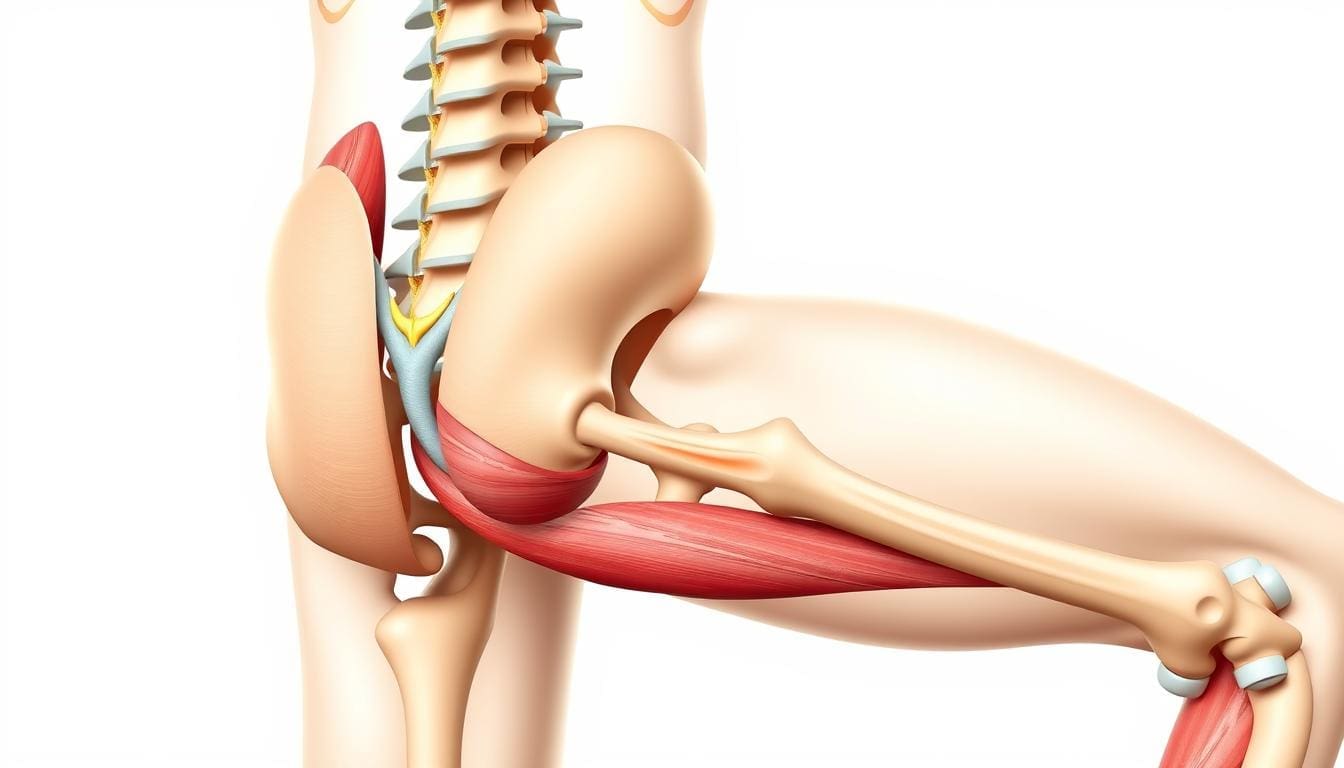

The Anatomy of the Lower Back and Leg Connection

The lower back, or lumbar region, is made up of vertebrae, discs, muscles, and nerves. The sciatic nerve, running from the lower back to the legs, is very important. When this nerve gets irritated or compressed, it can cause pain, numbness, or weakness in the legs.

Sciatica is pain that spreads along the sciatic nerve. This nerve runs from the lower back, through the hips, and down each leg. Sciatica is often linked to lower back pain and happens when the nerve roots get irritated.

Piriformis Syndrome

Piriformis syndrome is when the piriformis muscle in the buttock irritates or compresses the sciatic nerve. This can lead to pain, numbness, and tingling in the legs.